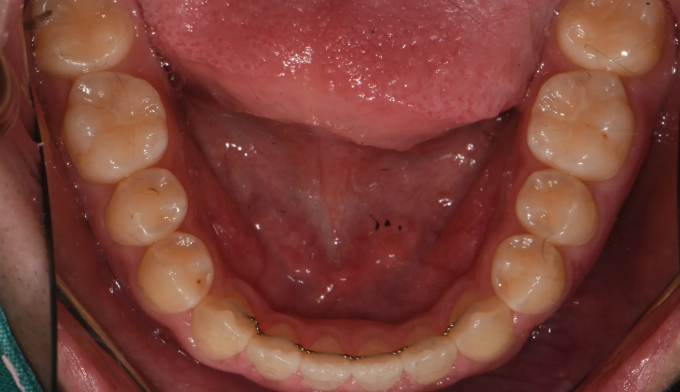

주걱턱 경향을 갖는 청소년들은 개방교합과 덧니를 동시에 갖는 경우가 많습니다. 아래턱의 과도한 성장은 혀의 위치를 아래로 처지게 만들고, 이는 위턱의 폭을 줄어들게 만들어 덧니가 생기기 쉽게 만듭니다. 그리고 과도한 아래턱의 성장은 앞니의 교합을 벌어지게 만들어 개방교합 또한 나타나게 됩니다.

그 정도에 따라 발치가 필요한 경우도 있지만, 성장기의 청소년의 경우에는 최대한 발치 없이 자연스러운 치열과 입매를 만드려고 합니다.

좁아진 위턱 악궁을 확장시켜서 치아를 배열시키고, 과도하게 앞으로 나온 앞니를 미니스크류를 이용하여 후방이동 시킵니다.

총 치료기간은 24개월 소요되었습니다.